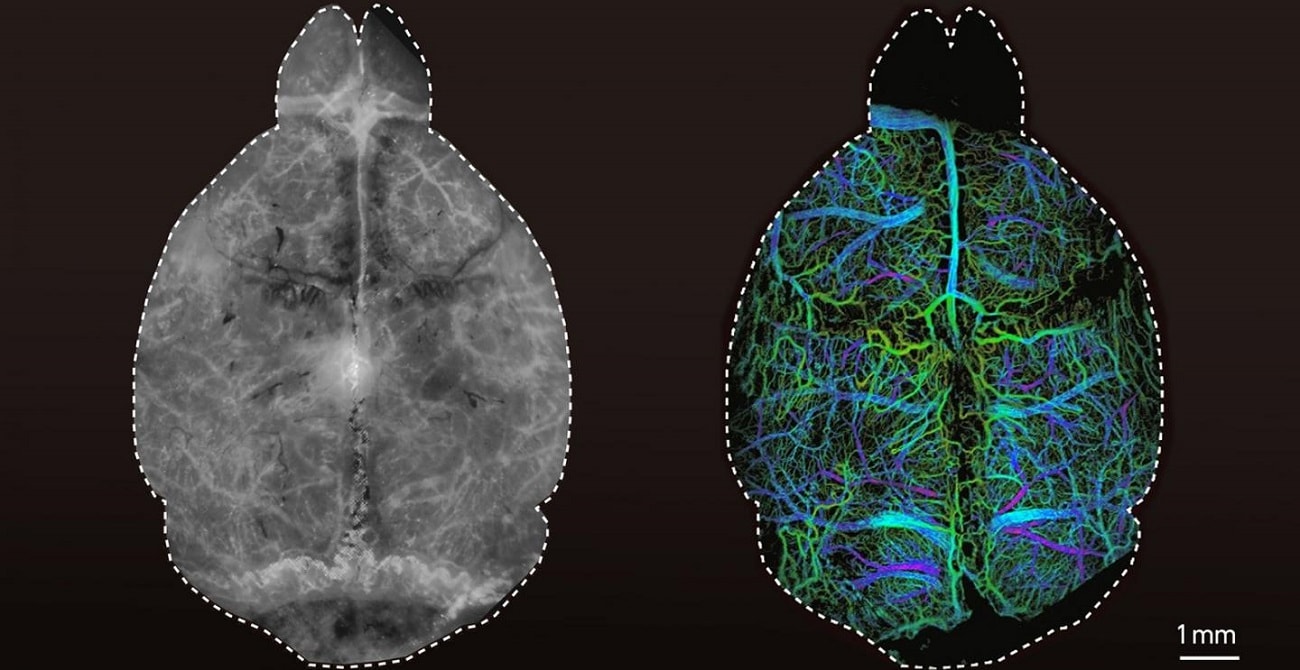

Długotrwały pobyt w przestrzeni kosmicznej wiąże się ze zmianami w mózgu